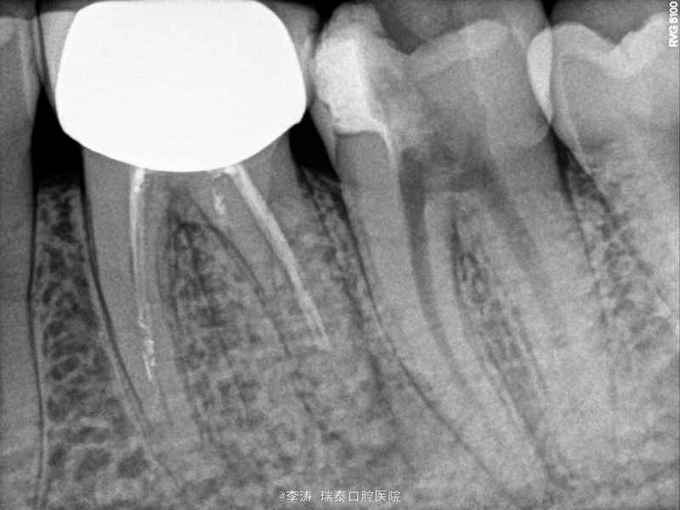

37牙去龋未净时穿髓 行根管治疗,开髓,根管预备,但根管预备封药后两天开始疼痛,叩痛明显,去除封药,未见明显分泌物,根管荡洗干燥后重新封药,但症状一直持续,自服止疼药后缓解,两周以后疼痛消失予以根充

根管封药后疼痛的原因?药物导致的根尖周炎?合创伤?预备时器械超出根尖孔导致的组织损伤?细菌感染? 怎样才能做到每次就诊封药后不疼?这真是一个值得考虑的问题